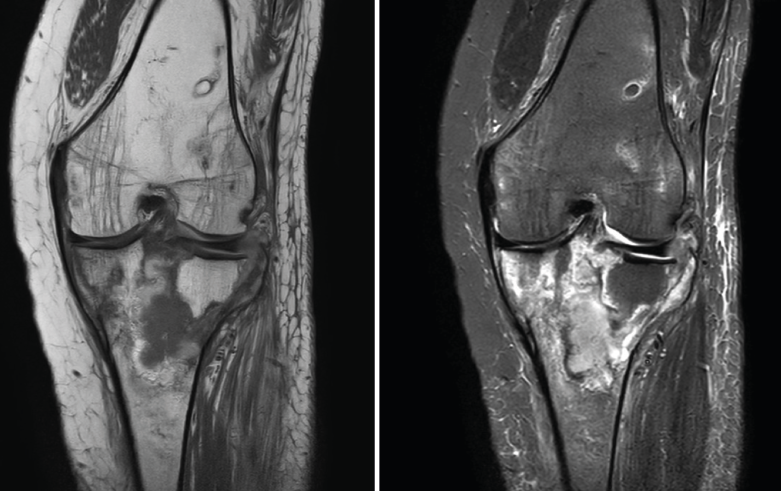

5. Tumores: óseos y de partes blandas

Figura 55. Corte de secuencia coronal T1 y STIR de resonancia magnética de rodilla: masa metafisaria tibial con fractura sobreañadida en la epífisis tibial proximal.

La RM es útil en las lesiones tumorales para determinar la extensión local (Figuras 55 y 56).

Figura 56. Corte de secuencia T2 Fat-Sat de resonancia magnética de rodilla: masa con intensidad de señal de grasa por gran lipoma localizado en la parte alta de la bursa suprapatelar.